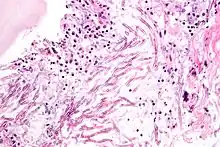

Une mycose est une infection fongique provoquée par une ou plusieurs espèces de microchampignons parasites ou saprophytes. Les pathologies fongiques étudiées par la mycologie médicale, sont souvent subdivisées en infections appelées superficielles, mycoses sous-cutanées et mycoses systémiques[1]. Elles concernent le plus souvent de petites zones de la peau et/ou des muqueuses. Beaucoup plus rarement le champignon envahit des organes internes (quand il s'agit des poumons ils peuvent y provoquer une infection évoquant une pneumonie ou une tuberculose pulmonaire).